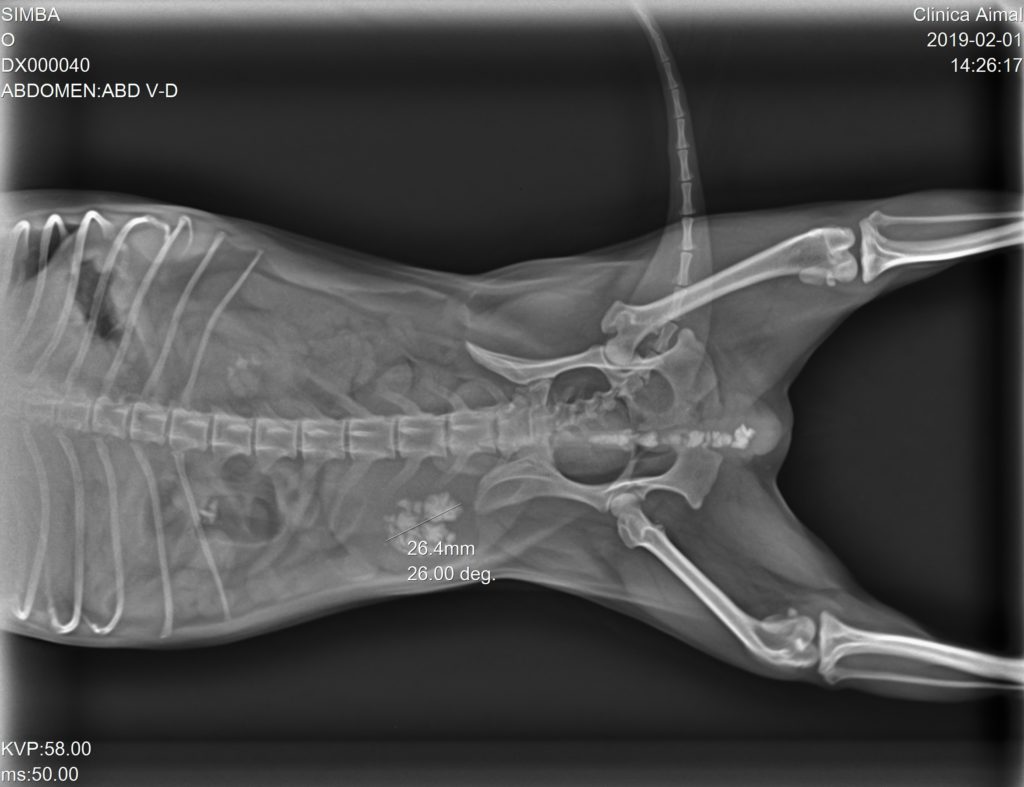

En la Rx pudimos observar gran cantidad de urolitos en la vejiga de la orina y uretra, depositándose en la parte más caudal del hueso peneano provocando una obstrucción incompleta:

Se sonda al animal para arrastrar mediante sonda y suero fisiológico a los cálculos de nuevo a la vejiga de la orina. Una vez realizado esto y contrastado mediante Rx, se pone tratamiento antibiótico, antiinflamatorio y se les cita para cirugía, en la cual se realizará una cistotomía y así retirar todos los cálculos.